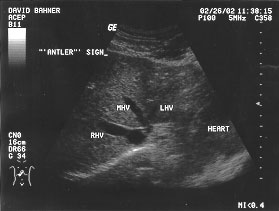

IVC and hepatic veins - leadin at IVC (labeled)